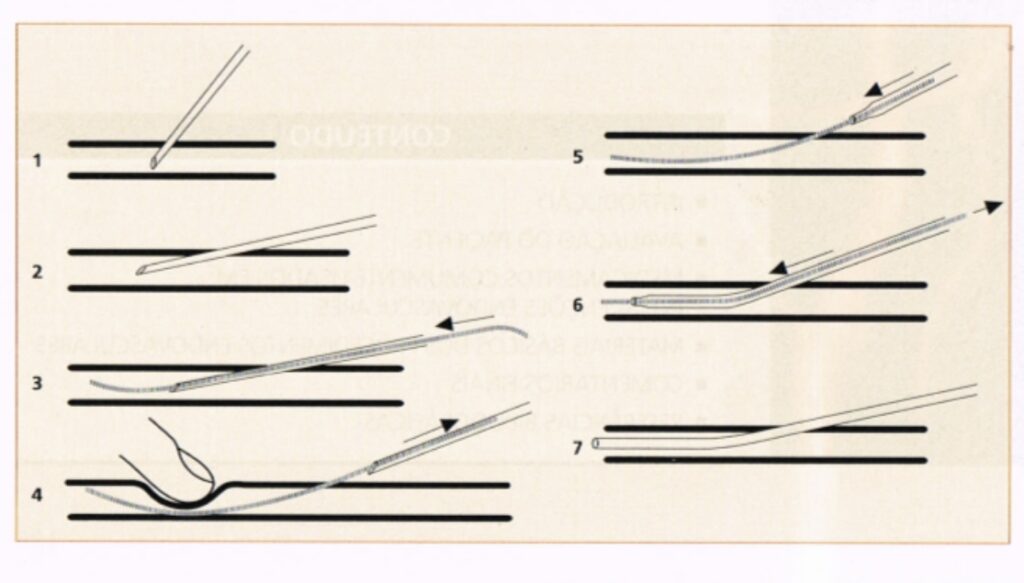

No que diz respeito a diagnóstico, os métodos de imagem não invasivos, como a Ultrassom (US) Doppler, a angiotomografia computadorizada (ATC) e a angiorressonância magnética (ARM), têm conquistado cada vez mais espaço na avaliação diagnóstica das patologias vasculares e reduzido o número de angiografias com subtração digital diagnósticas. Certamente, estas mudanças apresentam um avanço da medicina moderna, com inúmeras vantagens para os pacientes. No entanto, mesmo com todo esse avanço dos exames de imagem, ainda existem situações em que a angiografia continua sendo essencial. Isso acontece porque ela permite uma visualização direta e detalhada do interior dos vasos sanguíneos, com alta precisão, além de possibilitar que o diagnóstico e o tratamento sejam feitos no mesmo momento, quando necessário. Em casos complexos, quando há dúvidas nos exames não invasivos ou quando é preciso avaliar exatamente como o sangue está circulando em áreas críticas, vasos de calibre reduzido ou em localização de difícil acesso, a angiografia permanece como o método mais confiável e definitivo. Por isso, seu papel segue decisivo em cenários onde a segurança, a clareza diagnóstica e a tomada rápida de decisão são fundamentais para o melhor cuidado ao paciente.

• Angiografia digital diagnóstica, como complemento à US Doppler, ATC ou ARM.

• Angioplastia percutânea com stents (doença vascular arterial/venosa periférica: renal, carotídea, aorta torácica e abdominal entre outros).